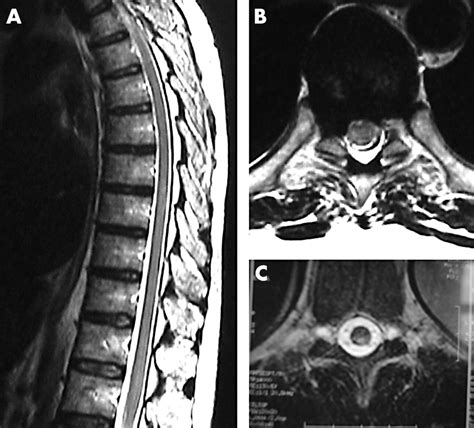

• Imaging Studies: MRI or CT scans to visualize the spinal cord and identify the location and extent of the injury.